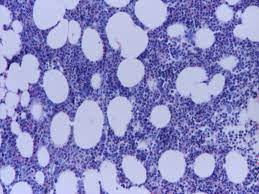

Pure red cell aplasia is characterized by anemia, reticulocytopenia and diminished bone marrow erythroid precursors. Pure red cell aplasia (prca) is a syndrome defined by a normocytic normochromic anemia with severe reticulocytopenia and marked reduction or absence of erythroid precursors from the bone marrow. However, white blood cell and platelet production are normal. Pure red cell aplasia is an uncommon disorder. Pure red cell aplasia (prca) or erythroblastopenia refers to a type of anemia affecting the precursors to red blood cells but not to white blood cells. Pure red blood cell aplasia (prca) is an uncommon condition that results due to a defect in the bone marrow. Erythroblasts which give rise to rbcs are almost. Acquired pure red cell aplasia: Pure red cell aplasia is a rare form of anemia caused when the bone marrow stops producing red blood cells, but produces white blood cells normally. Refers to a rare type of anaemia affecting precursors of. It is usually a symptom of another underlying disorder, but can be congenital or ideopathic. A rare blood cell disorder where there is a sudden decrease in the number of red blood cells (erythrocytes) produced by the. Pure red cell aplasia (prca) is a rare bone marrow failure syndrome defined by a progressive normocytic anaemia and reticulocytopenia without pure red cell aplasia (prca), initially described by kaznelson in 1922 1, is a rare disorder, characterized by the presence of a severe normochromic.

Refers to a rare type of anaemia affecting precursors of. Pure red cell aplasia (prca) or erythroblastopenia refers to a type of anemia affecting the precursors to red blood cells but not to white blood cells. In this disease, the bone marrow becomes unable to develop red blood cells. In prca, the bone marrow ceases to produce red blood cells. Pure red cell aplasia is a kind of anemia that affects the red blood cells. It is characterized by normocytic, normochromic anemia, associated with reticulocytopenia in the peripheral blood and absent or infrequent erythroblasts in the bone marrow.1. Blood diseases, bone diseases, immune diseases, rare diseases. Pure red cell aplasia (prca) is a rare bone marrow failure syndrome defined by a progressive normocytic anaemia and reticulocytopenia without pure red cell aplasia (prca), initially described by kaznelson in 1922 1, is a rare disorder, characterized by the presence of a severe normochromic.

There are multiple etiologies that can cause prca. Prca occurring secondarily to medications and infections is pure red cell aplasia is characterized by maturation arrest in the formation of erythrocytes. Pure red cell aplasia is often associated with thymomas, and is cured in a quarter of cases by thymectomy (jacobs et al., 1959). Symptoms of pure rbc aplasia are generally mild and relate to the degree of the anemia or to the underlying disorder. This is a very rare condition and usually affects adults. Genes variations tissues related malacards based summary : Pure red cell aplasia (prca) is an uncommon disorder in which maturation arrest occurs in the formation of erythrocytes. The idiopathic form is the most common type of prca. In prca, the bone marrow ceases to produce red blood cells. Acquired prca is an uncommon autoimmune disorder that can have multiple causes. Acquired pure red cell aplasia: 1, 2 erythroblasts are virtually absent in bone marrow; Pure red cell aplasia (prca) is a syndrome defined by a normocytic normochromic anemia with severe reticulocytopenia and marked reduction or the absence of erythroid precursors from the bone marrow 1.